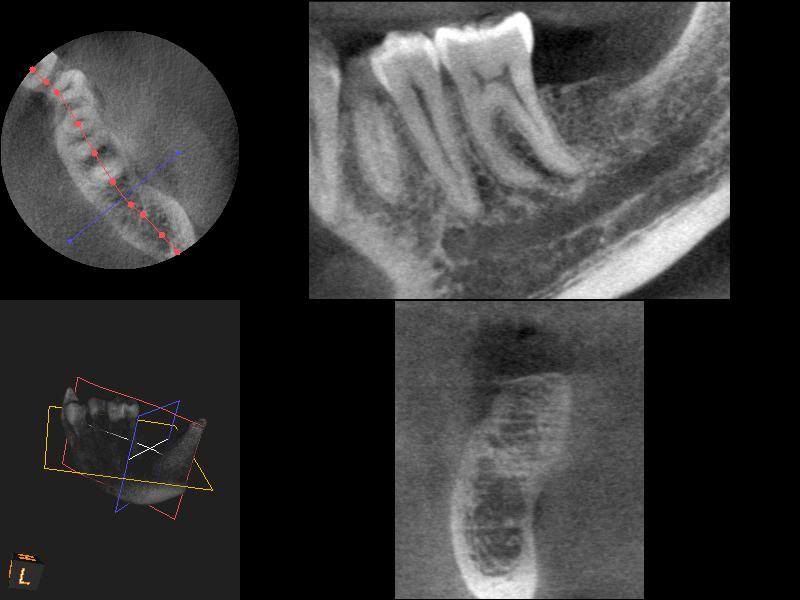

From www.researchgate.net

Class V amalgam filled teeth that were imaged through MRI, were held in Amalgam Tooth Filling Mri 60 extracted teeth were restored with three different types of amalgam filling materials. Metal dental fillings leak mercury if they are exposed to a new powerful type of medical scan, scientists have found. we found a significant increase in the release of mercury from dental amalgam fillings if mri is done within 24. however, mri is not. Amalgam Tooth Filling Mri.